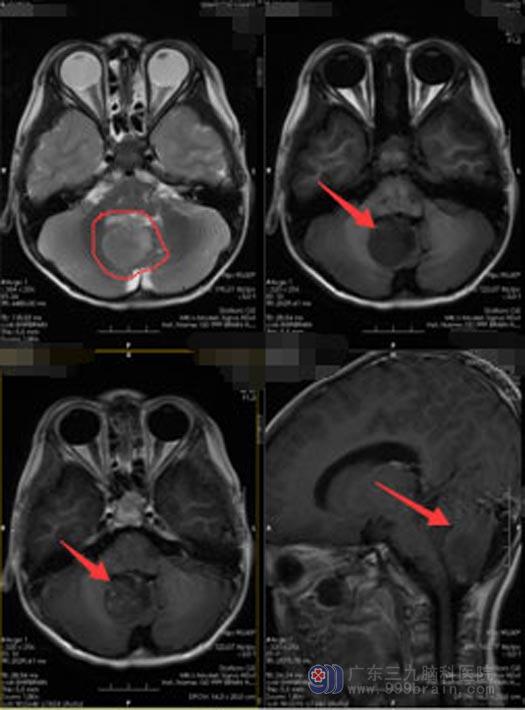

2月的一天,明明不小心摔伤了左前额,头皮裂伤,妈妈带着他去当地医院,头颅CT检查发现明明的小脑部位有一3.7cm×2.7cm×3.1cm大小、稍高密度占位病变。爸爸妈妈一下子惊呆了,本以为只是头皮的小擦伤,没想到宝宝的脑袋里居然有个这么大的肿瘤,联想到孩子之前说的种种不适,他们懊悔不已。

在广东三九脑科医院神经外五科,明明进行了进一步的影像检查,提示为:四脑室、小脑蚓部、右侧小脑半球占位。

肿瘤所在的位置有丰富的血管和神经,周围毗邻脑干等重要结构,稍有不慎,会损伤脑干、血管及神经,出现严重的并发症。完善术前检查后,由医院副院长、神经外五科主任鲁明主刀在全麻下行“四脑室、小脑蚓部、右侧小脑半球占位切除术”,术中见肿瘤自四脑室侵犯至小脑蚓部及右侧小脑半球,肿瘤顺利全切,血管保护好,脑干及颅神经无损伤。术后病理提示:室管膜瘤,WHOII级,术后复查头颅MRI:肿瘤全切。